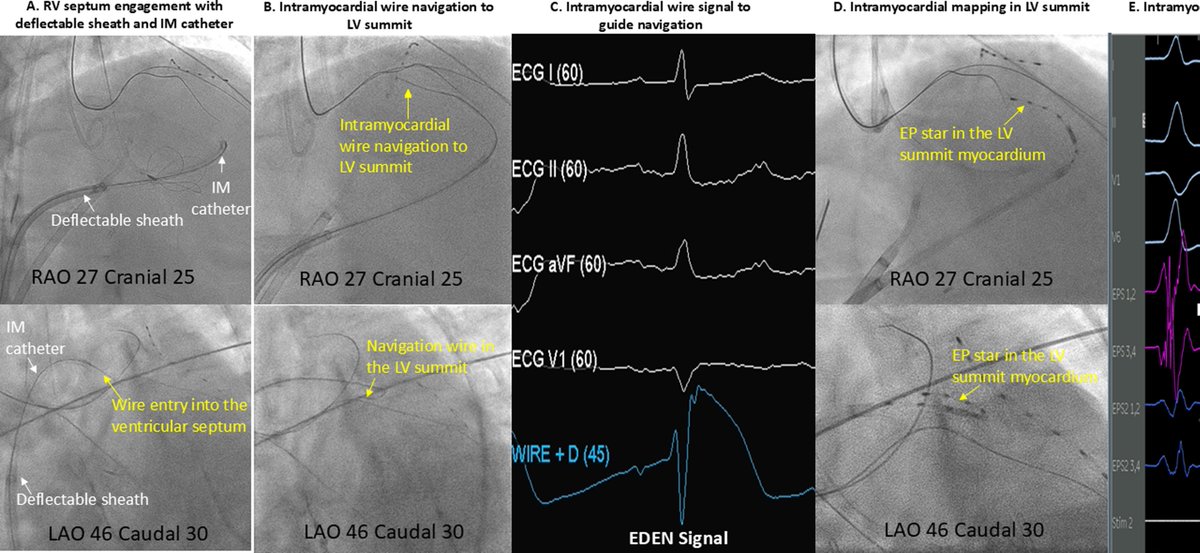

"Roads...where we are going, we don't need roads." Happy to share our work @rimhalabymd @ChrisGBruce13 using VINTAGE for intramural VAs - first in human. We demonstrated that we can successfully navigate to "inaccessible" areas such as the LV summit, deep septum, and papillary

Ventricular Intramyocardial Navigation for Tachycardia Ablation Guided by Electrograms (VINTAGE) for Left Ventricular Summit Arrythmia in a Human @danealson https://t.co/i0rf7JhHhV